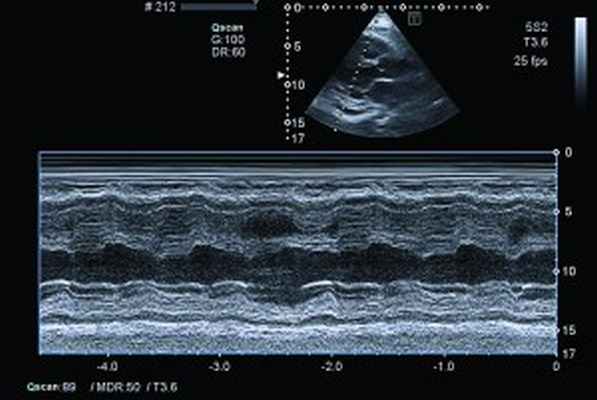

Рис. 4. Сохраненная кинетика стенок ЛЖ, гидроперикард по ЗСЛЖ (парастернальный доступ, позиция по длинной оси, М-режим)

ЭхоКГ: Патологические изменения миокарда ПЖ с утолщением стенок до 18 мм. Диффузный гипокинез стенок ЛЖ с дискинезом верхушки – ФВ 44%. В области верхушки ПЖ – наслоения между листками перикарда. Небольшое количество жидкости в полости перикарда – по ЗСЛЖ до 5 мм. Таким образом, в динамике на ЭхоКГ наблюдалось снижение сократительной функции ЛЖ на фоне его гипертрофии и, несмотря на проведенную высокодозовую терапию гормонами, не уменьшилась гипертрофия ПЖ.